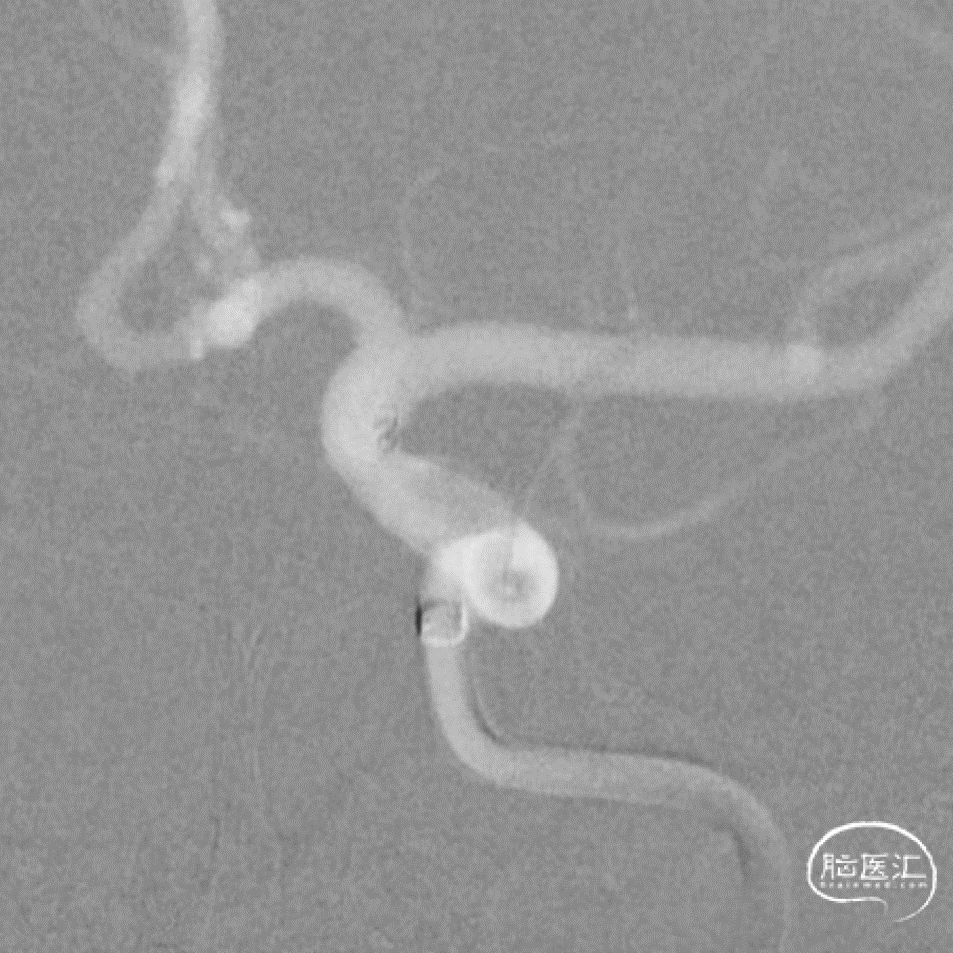

工作角度造影

数值测量

Roadmap

支架远端定位和释放

释放过程

术后即刻

术后即刻支架形态